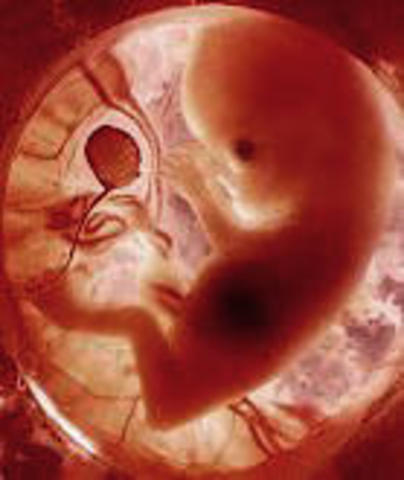

Video:Día 1-28El embarazo humano comienza con la fusión de un óvulo y un espermatozoide, a este proceso se le llama fecundación, cuando el óvulo es fecundado, un nombre mas apropiado es el de embrión. Éste ha de entrar al útero, donde se sumerge en la capa de revestimento interno del útero para ser nutrido por la madre.

• 12 semanas. Características externas

12 semanas. Características externas

-La cabeza está erguida

-El cuello está casi derecho y bien definido

-El oído externo se está formando y de ha desplazado hasta cerca de su posición definitiva en la cabeza

-El saco vitelino se ha encogido

-El foto deglute líquido amniótico

-El feto puede responder a la estimulación de la piel